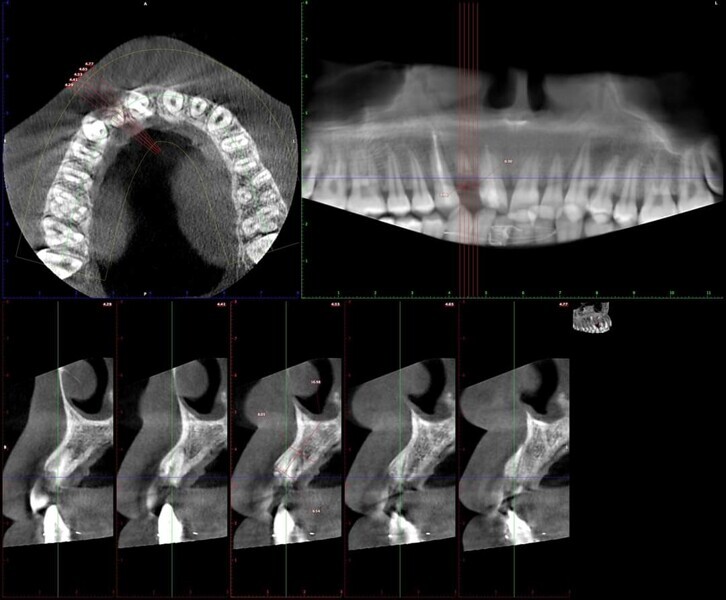

Esthetic Rehabilitation of Maxillary Anterior Teeth: Dr Sanjay Sah